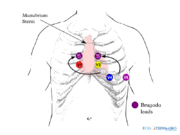

| 09:21, 9 October 2012 | Brugada lead placement.png (file) |  |

84 KB | 1 | |